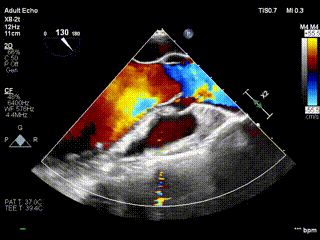

视频5:病例3术前大量主动脉瓣反流

视频6:病例3术后未见反流